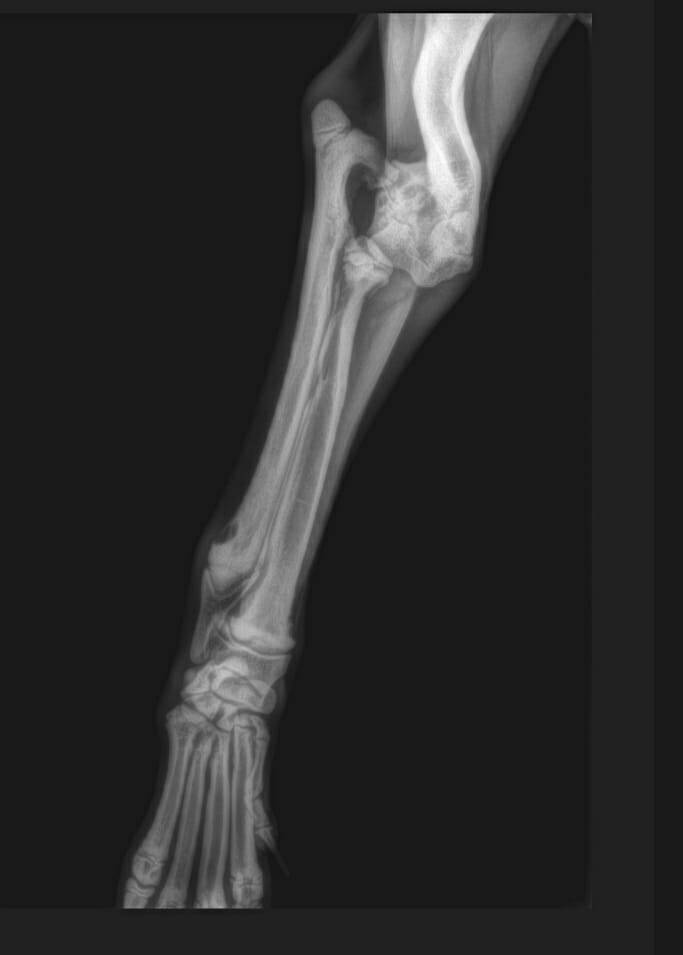

Der kleine Mickey war erst ca. 4 Wochen alt und musste in seinem kurzen Leben schon viel aushalten. Seine Rute wurde abgeschnitten und sein Vorderbein war ausgerenkt. Wir waren deshalb direkt bei unserem Knochenspezialisten, der versucht hat, das kleine Beinchen wieder einzurenken. Leider hat dies nicht geklappt und Mickey bekommt aktuell Physiotherapie.

Eine erneute Untersuchung und Röntgen im Juni 2022 haben gezeigt, dass seine Knochen im Vorderbein so verdreht sind, dass eine Operation nicht erfolgversprechend ist. Aktuell kann Mickey mit seinem Handicap schmerzfrei und mit wenigen Einschränkungen gut leben. Er bekommt zusätzliche Vitamine aber es ist möglich, dass sich sein Ellbogengelenk mit zunehmendem Gewicht entzündet und eine Amputation des Beines notwendig wird.